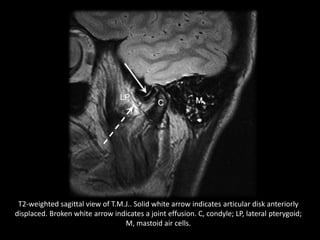

T2-weighted sagittal view of T.M.J.. Solid white arrow indicates articular disk anteriorly

displaced. Broken white arrow indicates a joint effusion. C, condyle; LP, lateral pterygoid;

M, mastoid air cells.